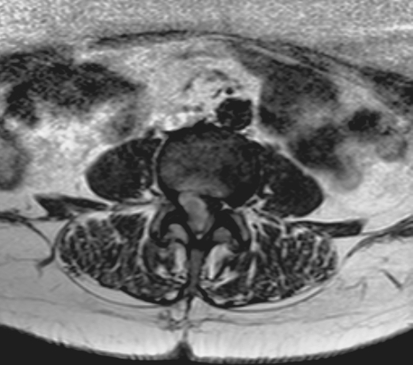

A lumbo-sacral (L1–S1) CT scan showed an inhomogeneous hypodense formation at the level of right L3–L4 neuroforamen. The patient underwent MRI which revealed a bilobar mass between L3 and L4, suggesting a lumbar Schwannoma extending to the right ipsilateral foramen (Figs. 1, 2).

Fig. 1.

Case 1, axial L3–L4 preoperative T1 MRI sequence